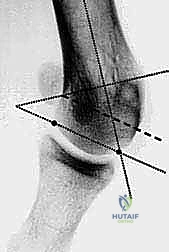

- القياسات الهندسية لزوايا القدم: يقوم الدكتور هطيف بقياس زوايا محددة لتحديد نوع الجراحة، أهمها:

- HVA (Hallux Valgus Angle): زاوية انحراف الإبهام (الطبيعي أقل من 15 درجة).

- IMA (Intermetatarsal Angle): الزاوية بين العظمة المشطية الأولى والثانية (الطبيعي أقل من 9 درجات).

- DMAA (Distal Metatarsal Articular Angle): زاوية سطح المفصل، وهي الزاوية الأهم التي تحدد الحاجة لتقنية "ش